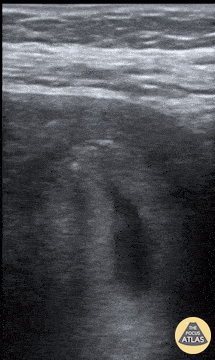

This trans abdominal ultrasound reveals a yolk sac. John Joseph, MD. University of Michigan